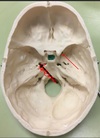

1. Identify the structure. 2. What produces this structure?

1. Petrous Crest 2. Sphenoid and occipital bones Arcuate Eminence due to Superior Semicircular Canal.

119

1. Identify the structure. 2. What structures traverse this canal?

1. Internal Acoustic Meatus 2. transmits the vestibulocochlear nerve, the facial nerve, and the labyrinthine artery (an internal auditory branch of the basilar artery). It also contains the vestibular ganglion. CN 7 & 8

120

1. Identify the structure. 2. What are the subdivisions of this structure? 3. What structures traverse these subdivisions?

1. Jugular Foramen, CN 9,10, 11 2. Anterior Intermediate, posterior 3. The anterior compartment transmits the inferior petrosal sinus and glossopharyngeal nerve (CN IX) The intermediate transmits the vagus and accessory nerves (aka cranial nerves number X, and XI respectively). The posterior transmits the sigmoid sinus (becoming the internal jugular vein) and some meningeal branches from the occipital and ascending pharyngeal arteries.

121

1. Identify the canal. 2. What structures traverse this canal?

1. Hypoglossal canal 2. Hypoglossal Nerve

122

1. Formaen Magnum 2. Spinal cord, CN11 accessory, vertebral arteries.

123